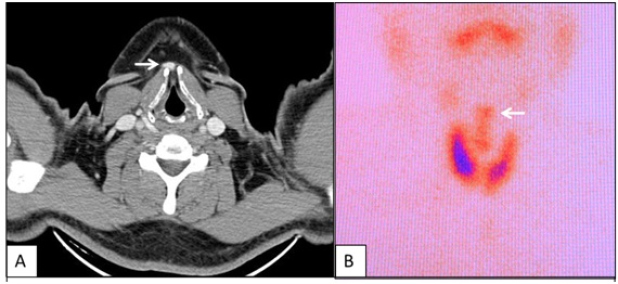

Caso 2: Paciente de sexo femenino de 41 año, con antecedente de tumoración cervical y lingual desde los 5 años, que cursa con disfagia, motivo por el cual se le realiza una gammagrafía tiroidea. Al examen se comprueba tumoración cervical alta palpable de 1,5 cm de diámetro aproximadamente, móvil con la deglución, no visible a la inspección simple; en base de lengua se evidencia otra tumoración (fig. 3A).En el estudio gammagráfico se identifican dos áreashipercaptantes (fig. 3B) que se correlacionan con tumoracionesobservadas al examen clínico. Se trató de un caso de tiroides ectópica doble.